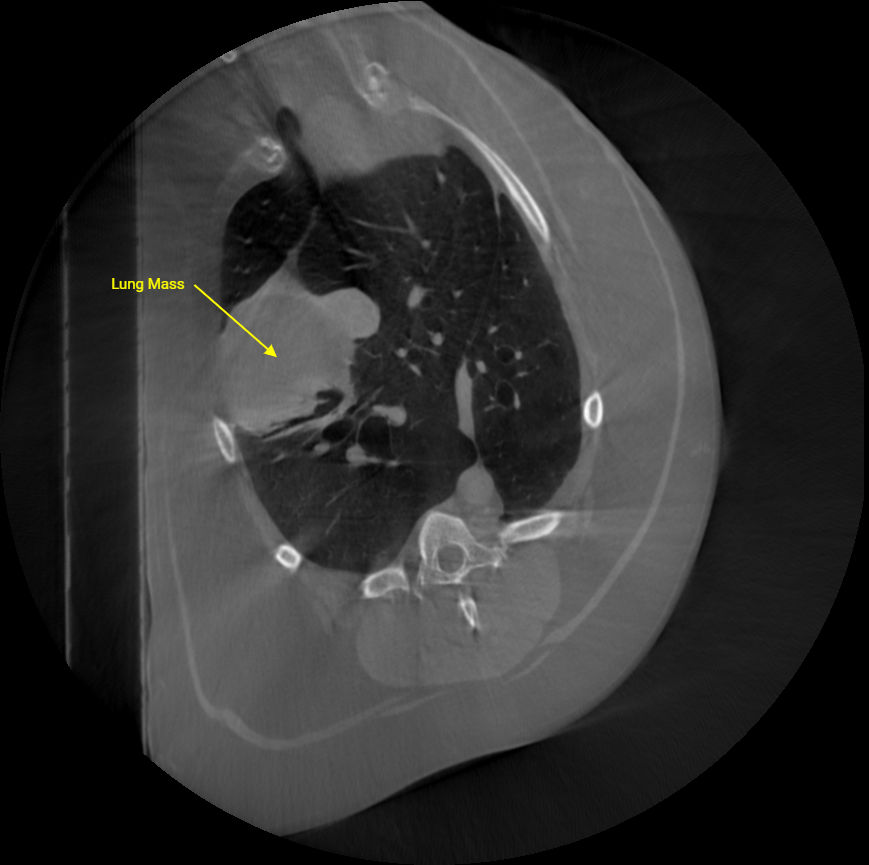

CT

Chest CT Demonstrating masses in the lungs.